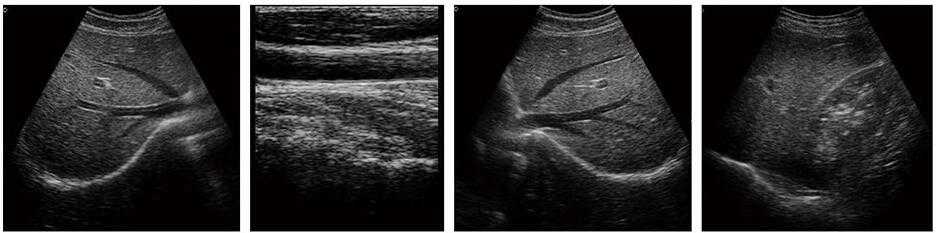

豐富的臨床應用

多倍率顯示,病變診斷更精確